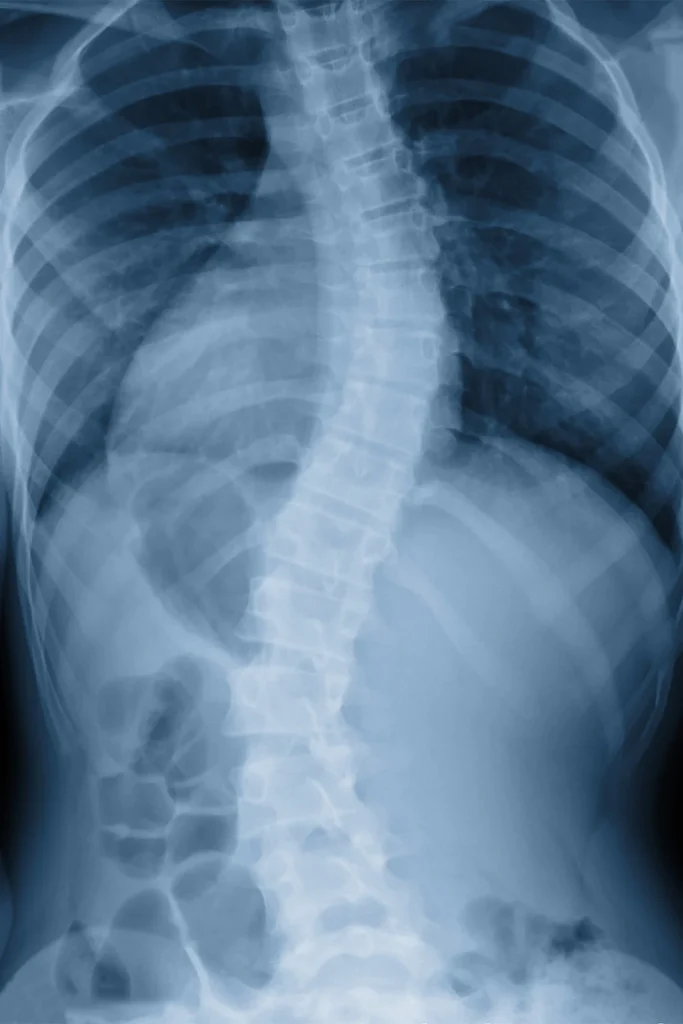

Sciatica refers to irritation or compression of the sciatic nerve — the longest nerve in the body — which runs from your lower back down through your hips, legs, and feet. It’s often caused by spinal misalignment, a herniated disc, or muscle tension putting pressure on the nerve.

We begin with a thorough evaluation of your spine, pelvis, and lower body mechanics. Digital X-rays may be taken to rule out disc involvement or structural problems. Treatment may include chiropractic adjustments, spinal decompression therapy, and soft tissue techniques to reduce inflammation, improve alignment, and relieve nerve irritation.